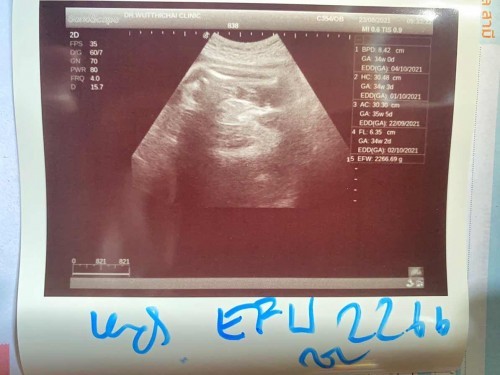

แม่ๆมีวิธีเพิ่มน้ำหนักลูกให้ขึ้นเร็วๆไหมคะ พอดีเราท้องได้ 36 week 3 day แล้ว แต่น้ำหนักลูกแค่2266 เอง แนะนำหน่อยค่ะ